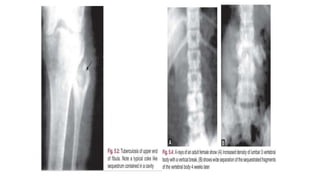

• X-ray of the affected part-in antero-posterior and lateral views and

x-ray of the chest are mandatory.

• In active disease -localized osteoporosis is the first radiological sign .

• The articular margins and bony cortices become hazy(giving‘’washed

out”) appearance and there is development of areas of trabecular or

bony destruction and osteolysis.

• Diminution of joint space in x-rays in area of articular cartilage